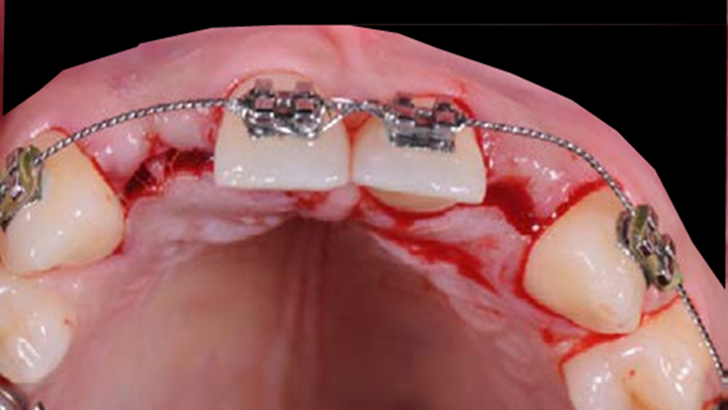

Clinical case: Patient-centered approach: treatment strategy for Root Membrane Technique & delayed implant placement

- Courtesy of Dr. Yoshiharu Hayashi, Japan -

Socket Shield Technique, anterior esthetics, maxillary anterior, esthetic, esthetics, delayed implant placement, socket preservation, AnyRidge, Root Membrane Kit, Root Membrane Technique, Partial Extraction Therapy, PET, esthetic zone, fuse abutment, Dr. Yoshiharu Hayashi,#11,#21,#22

AnyRidge implant system, fuse abutment Root membrane kit, PET Kit